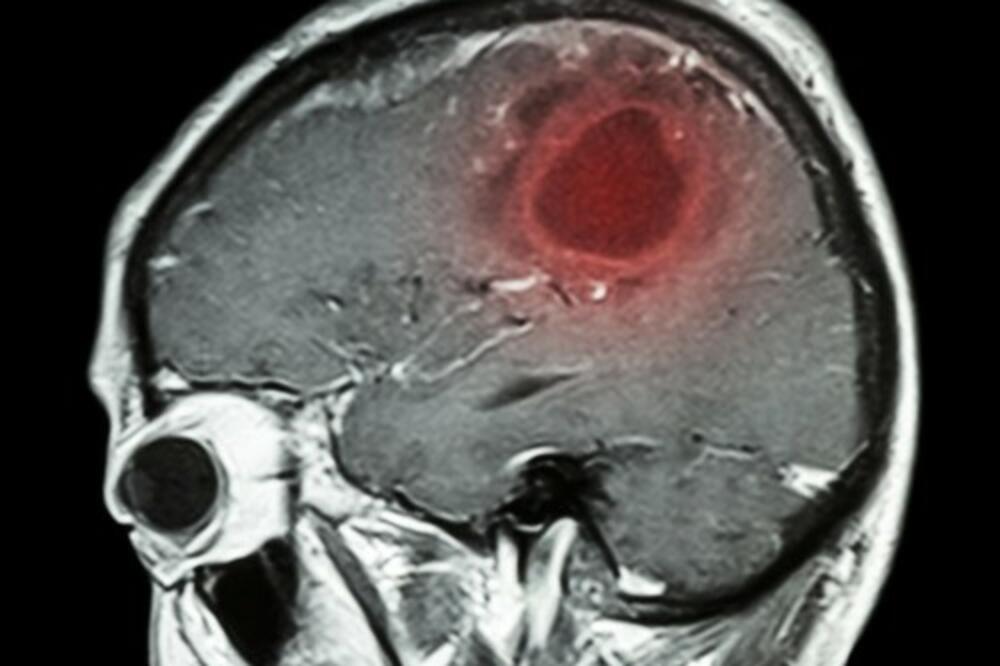

7 NAIZGLED BEZAZLENIH SIMPTOMA KOJI UKAZUJU NA TUMOR MOZGA: Važno je da ih prepoznate

Tumori na mozgu dolaze u različitim oblicima i veličinama, pa se tako razlikuju i njihovi simptomi. Kada je reč o simptomima, ključni faktor je mesto u mozgu na kojoj se tumor nalazi. Primera radi, ako se tumor nalazi u blizini centra za vid, verovatno je da će osoba imati probleme s vidom

Kada uzmemo u obzir da svaka stanica u mozgu može postati tumor i da sve informacije, iz svakog dela tela, putuju u njega i iz njega odlaze, jasno ti je da "popis potencijalnih simptoma tumora može biti beskonačan", izjavio je dr. med. Theodore Schwartz, neurohirurg, za womenshealthmag.com.